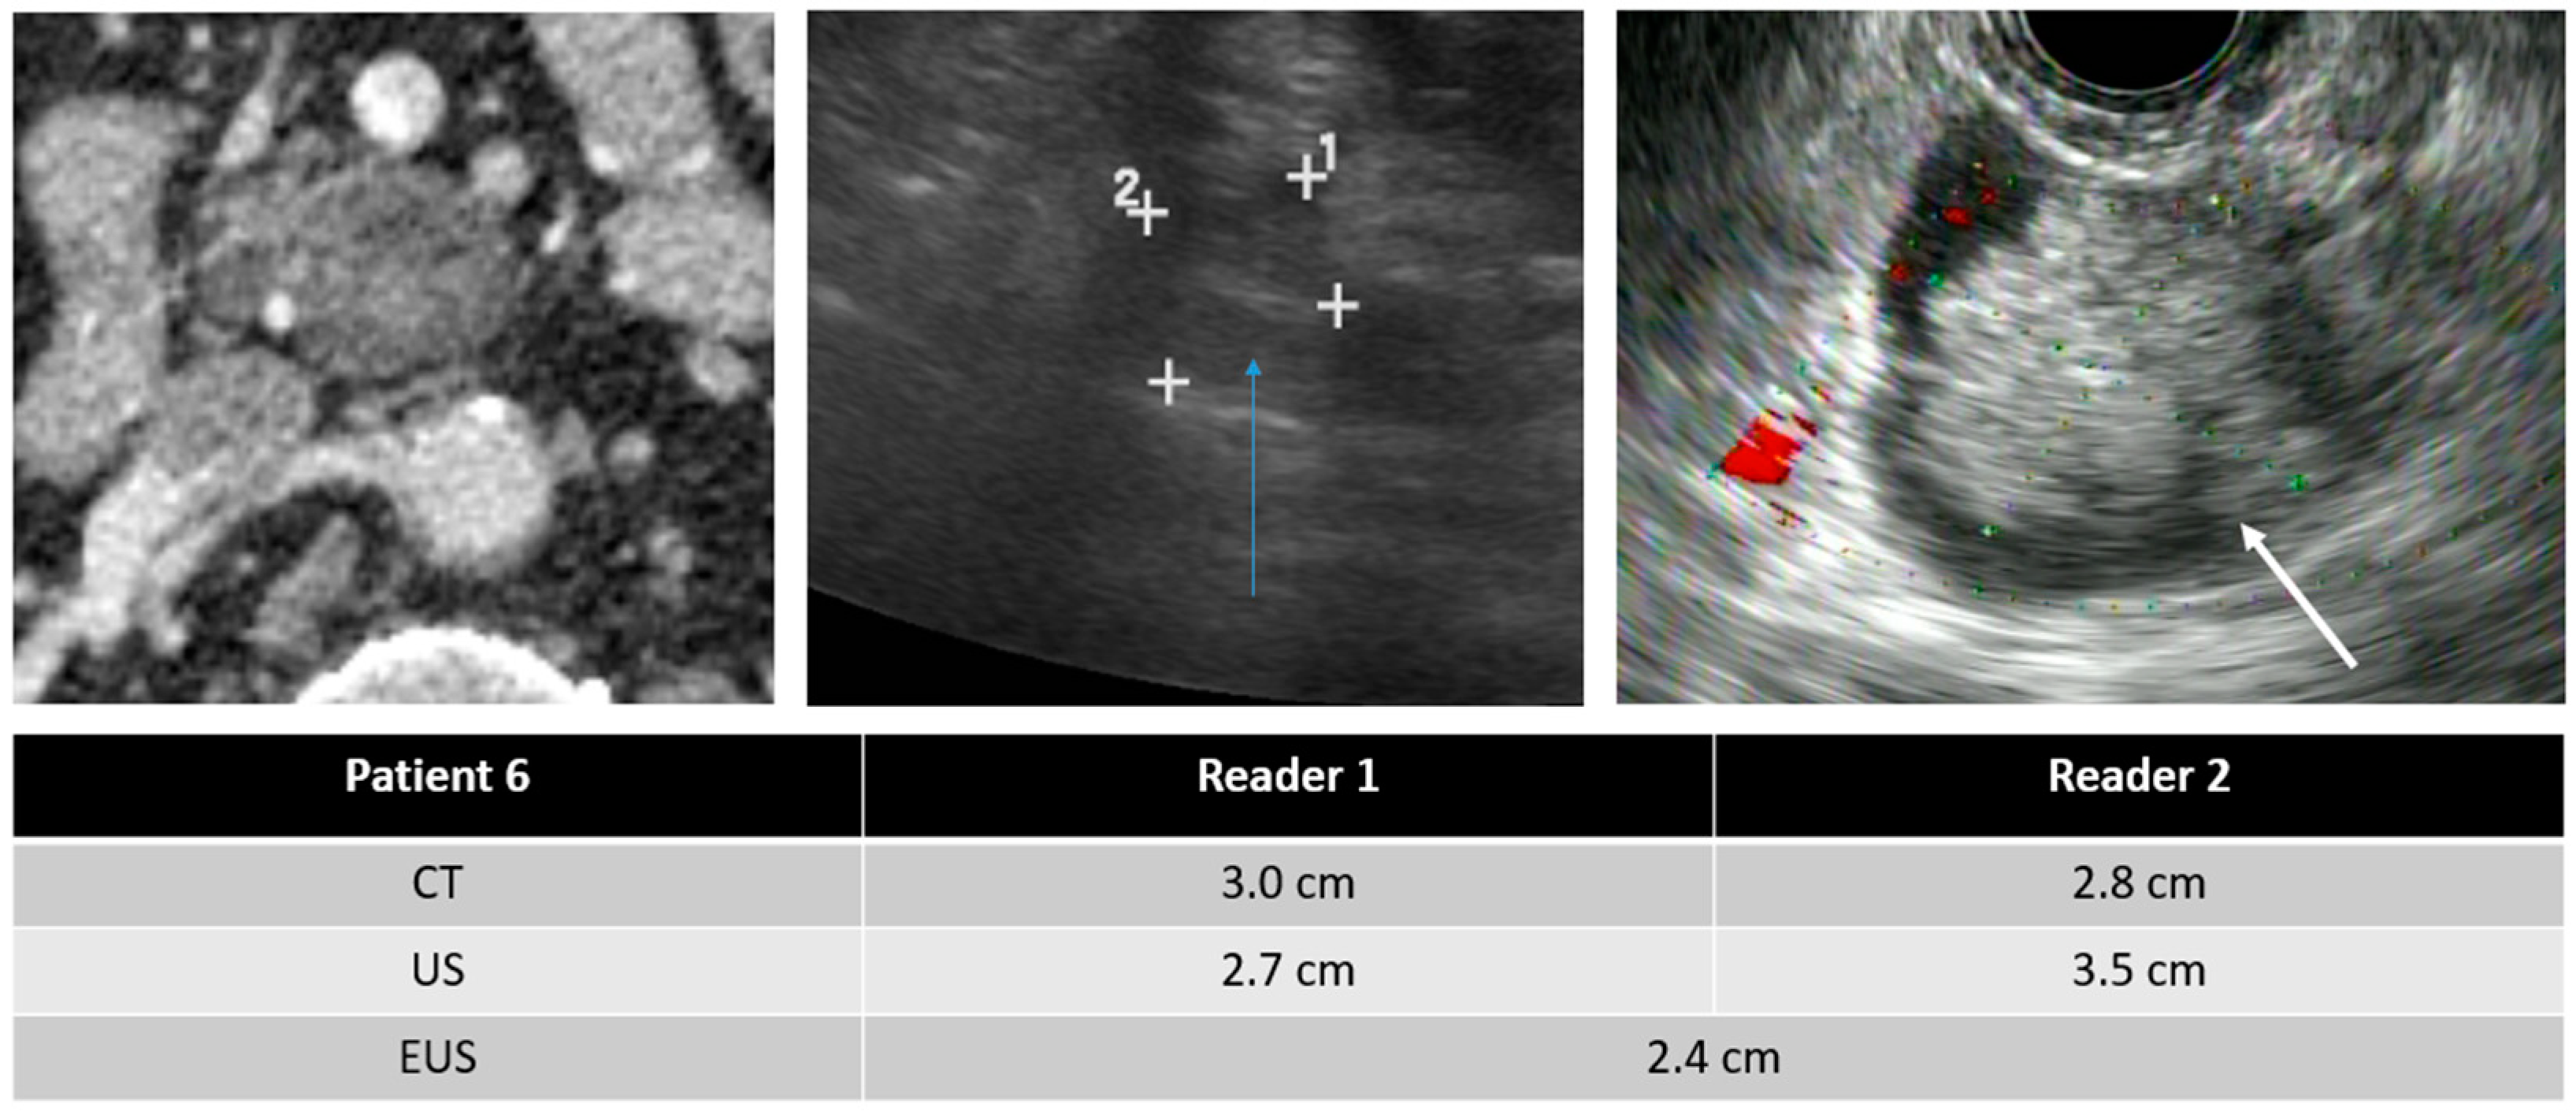

| Mean size of detected PCLs (cm) | ||

| TAUS | 2.40 ± 2.65 | 2.41 ± 2.56 |

| CT | 2.45 ± 2.43 | 2.48 ± 2.53 |

| EUS * | 2.73 ± 2.10 | |

| Intra-reader variability in measured size | Reader 1 vs. Reader 2 | |

| TAUS | −0.01 ± 0.39 | |

| TAUS vs. CT | TAUS vs. EUS | CT vs. EUS | |

| All PCLs (cm) | |||

| Reader 1 | −0.16 ± 0.53 * | 0.13 ± 1.14 | 0.15 ± 0.65 * |

| Reader 2 | −0.19 ± 0.55 * | 0.18 ± 0.81 | 0.22 ± 0.90 |